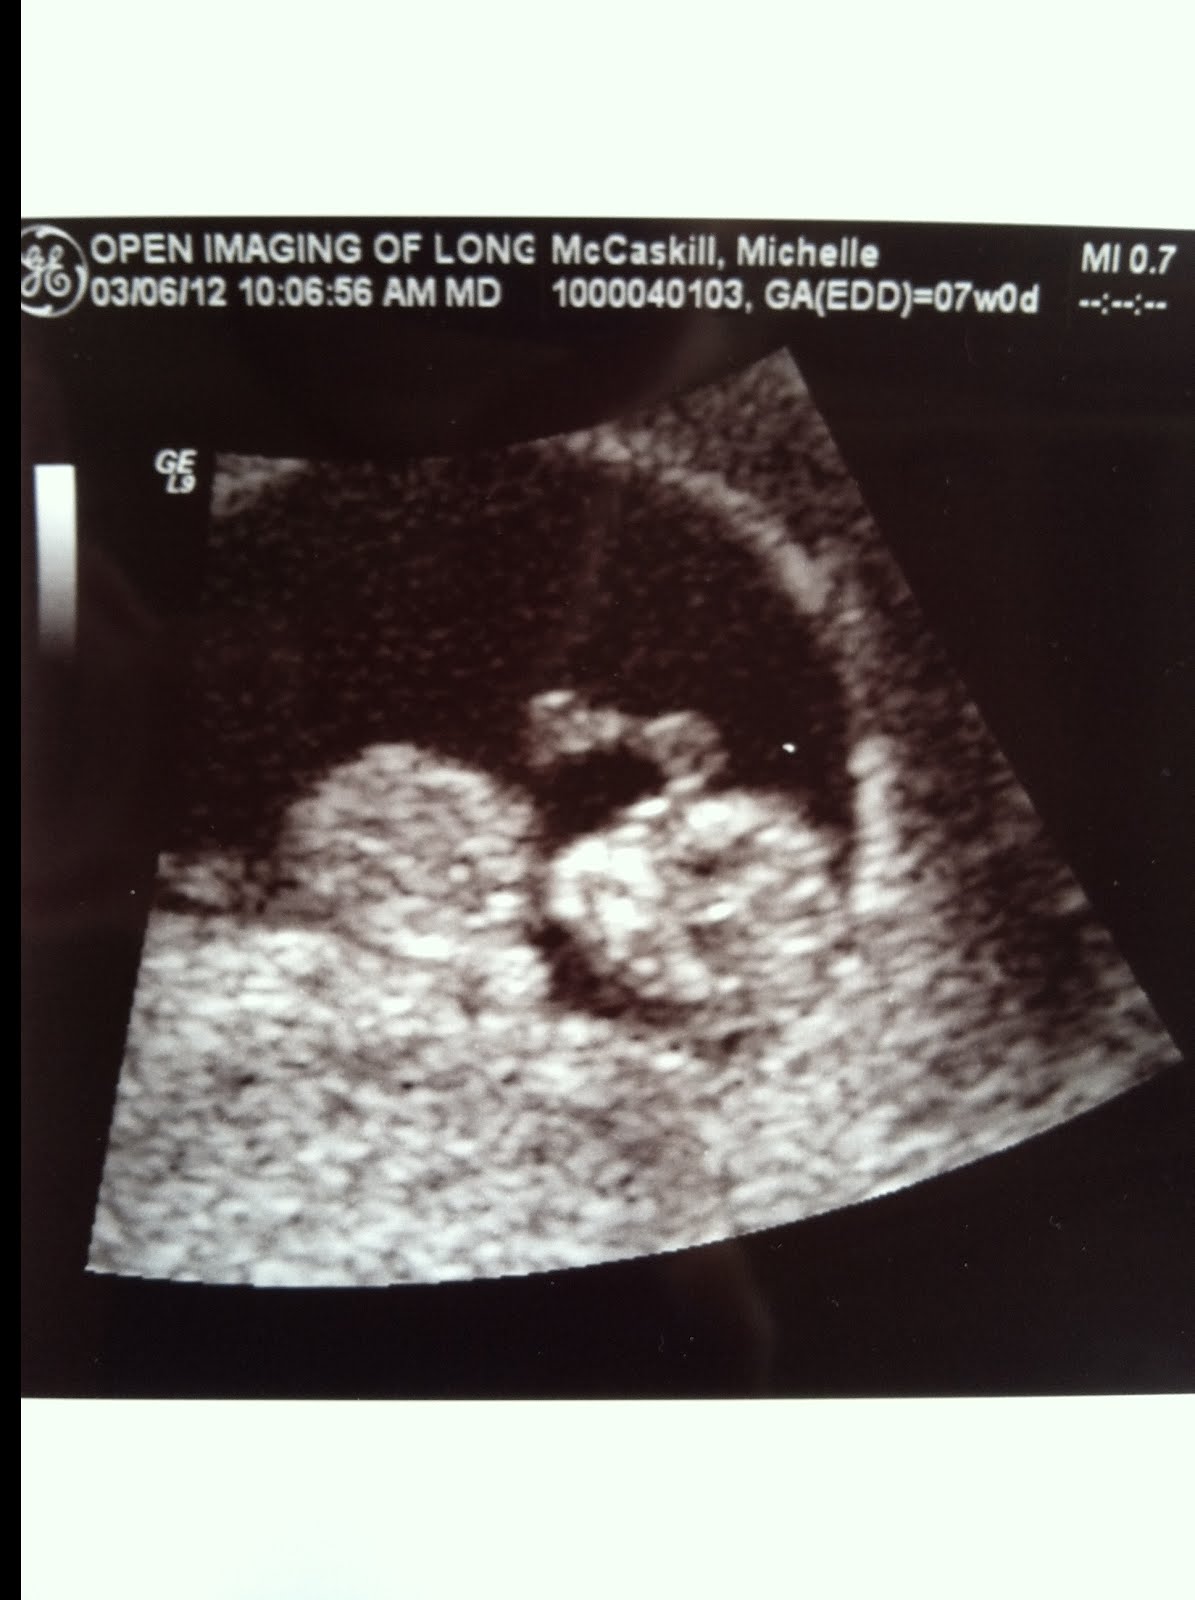

We have some very exciting news to share... we're pregnant! I've felt a strange loss of appetite over the past month or so, but didn't think much of it until I started to feel a little nauseous last week. I decided to take a pregnancy test & to my surprise, it was positive!! Because I was still nursing Casen & Collins, I had no idea how far along we were. We went in for a sonogram this morning to measure the baby & estimate his/her gestational age - it turns out that we are already 11 weeks along!